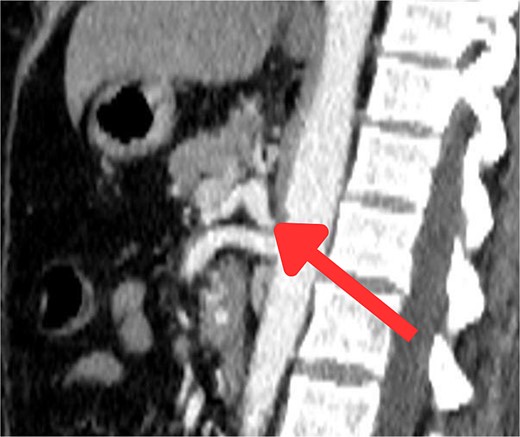

The CT scan confirmed a Dieulafoy’s lesion from the left phrenic artery (Fig. 2a and b) and showed collateral vascular channels around the pancreas with near-complete celiac trunk compression by the median arcuate ligament (Fig. 3). She underwent left phrenic artery embolization without complications, while asymptomatic celiac artery compression was treated conservatively. A follow-up endoscopy showed no bleeding or ulcers (Fig. 1d). Later, she developed severe left flank pain, and a contrast-CT revealed splenic vein thrombosis with infarction (Fig. 4), which was treated conservatively. Additionally, an incidental finding of left pleural effusion was drained. Rising inflammatory markers were managed with analgesics and IV antibiotics. She was discharged with outpatient follow-up, and at her 10-day visit, she reported improvement, stable hemoglobin, and normal inflammatory markers. She was satisfied, and a follow-up endoscopy was planned in 2 weeks.

(a) Axial CT angio of the abdomen shows a small area of enlarged tortuous blood vessels seen along the posterior cardia of the stomach; these findings are suggestive of Dieulafoy lesion. (b) Coronal abdominal CT images show the feeding blood vessel arising from the descending abdominal aorta located just superior to the origin of the left renal artery.